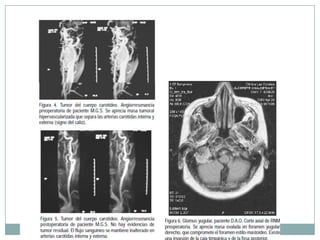

 Los paragangliomas son tumores benignos,

altamente vascularizados, cuyas células se originan

en la cresta neural embrionaria. Se ubican a lo largo

de arterias y pares craneales de los arcos

branquiales, siendo infrecuentes en la región

cérvicofacial.

 Frecuentes, de lenta evolución, que derivan del

sistema paraganglionar.

 Tratamiento de elección es la resección

quirúrgicacompleta, lo cual se ve dificultado por su

abundante irrigación y por su estrecha

relaciónanatómica con importantes estructuras

vásculo-nerviosas.

 El 90% de los paragangliomas (tumores originados

en tejdo paraganglionar) se ubica en laglándula

suprarrenal (feocromocitoma).

 El 85% delos paragangliomas extrasuprarrenales se

localiza

 en el abdomen, 12% en el tórax y, sólo un 3%

 cabeza y cuello.